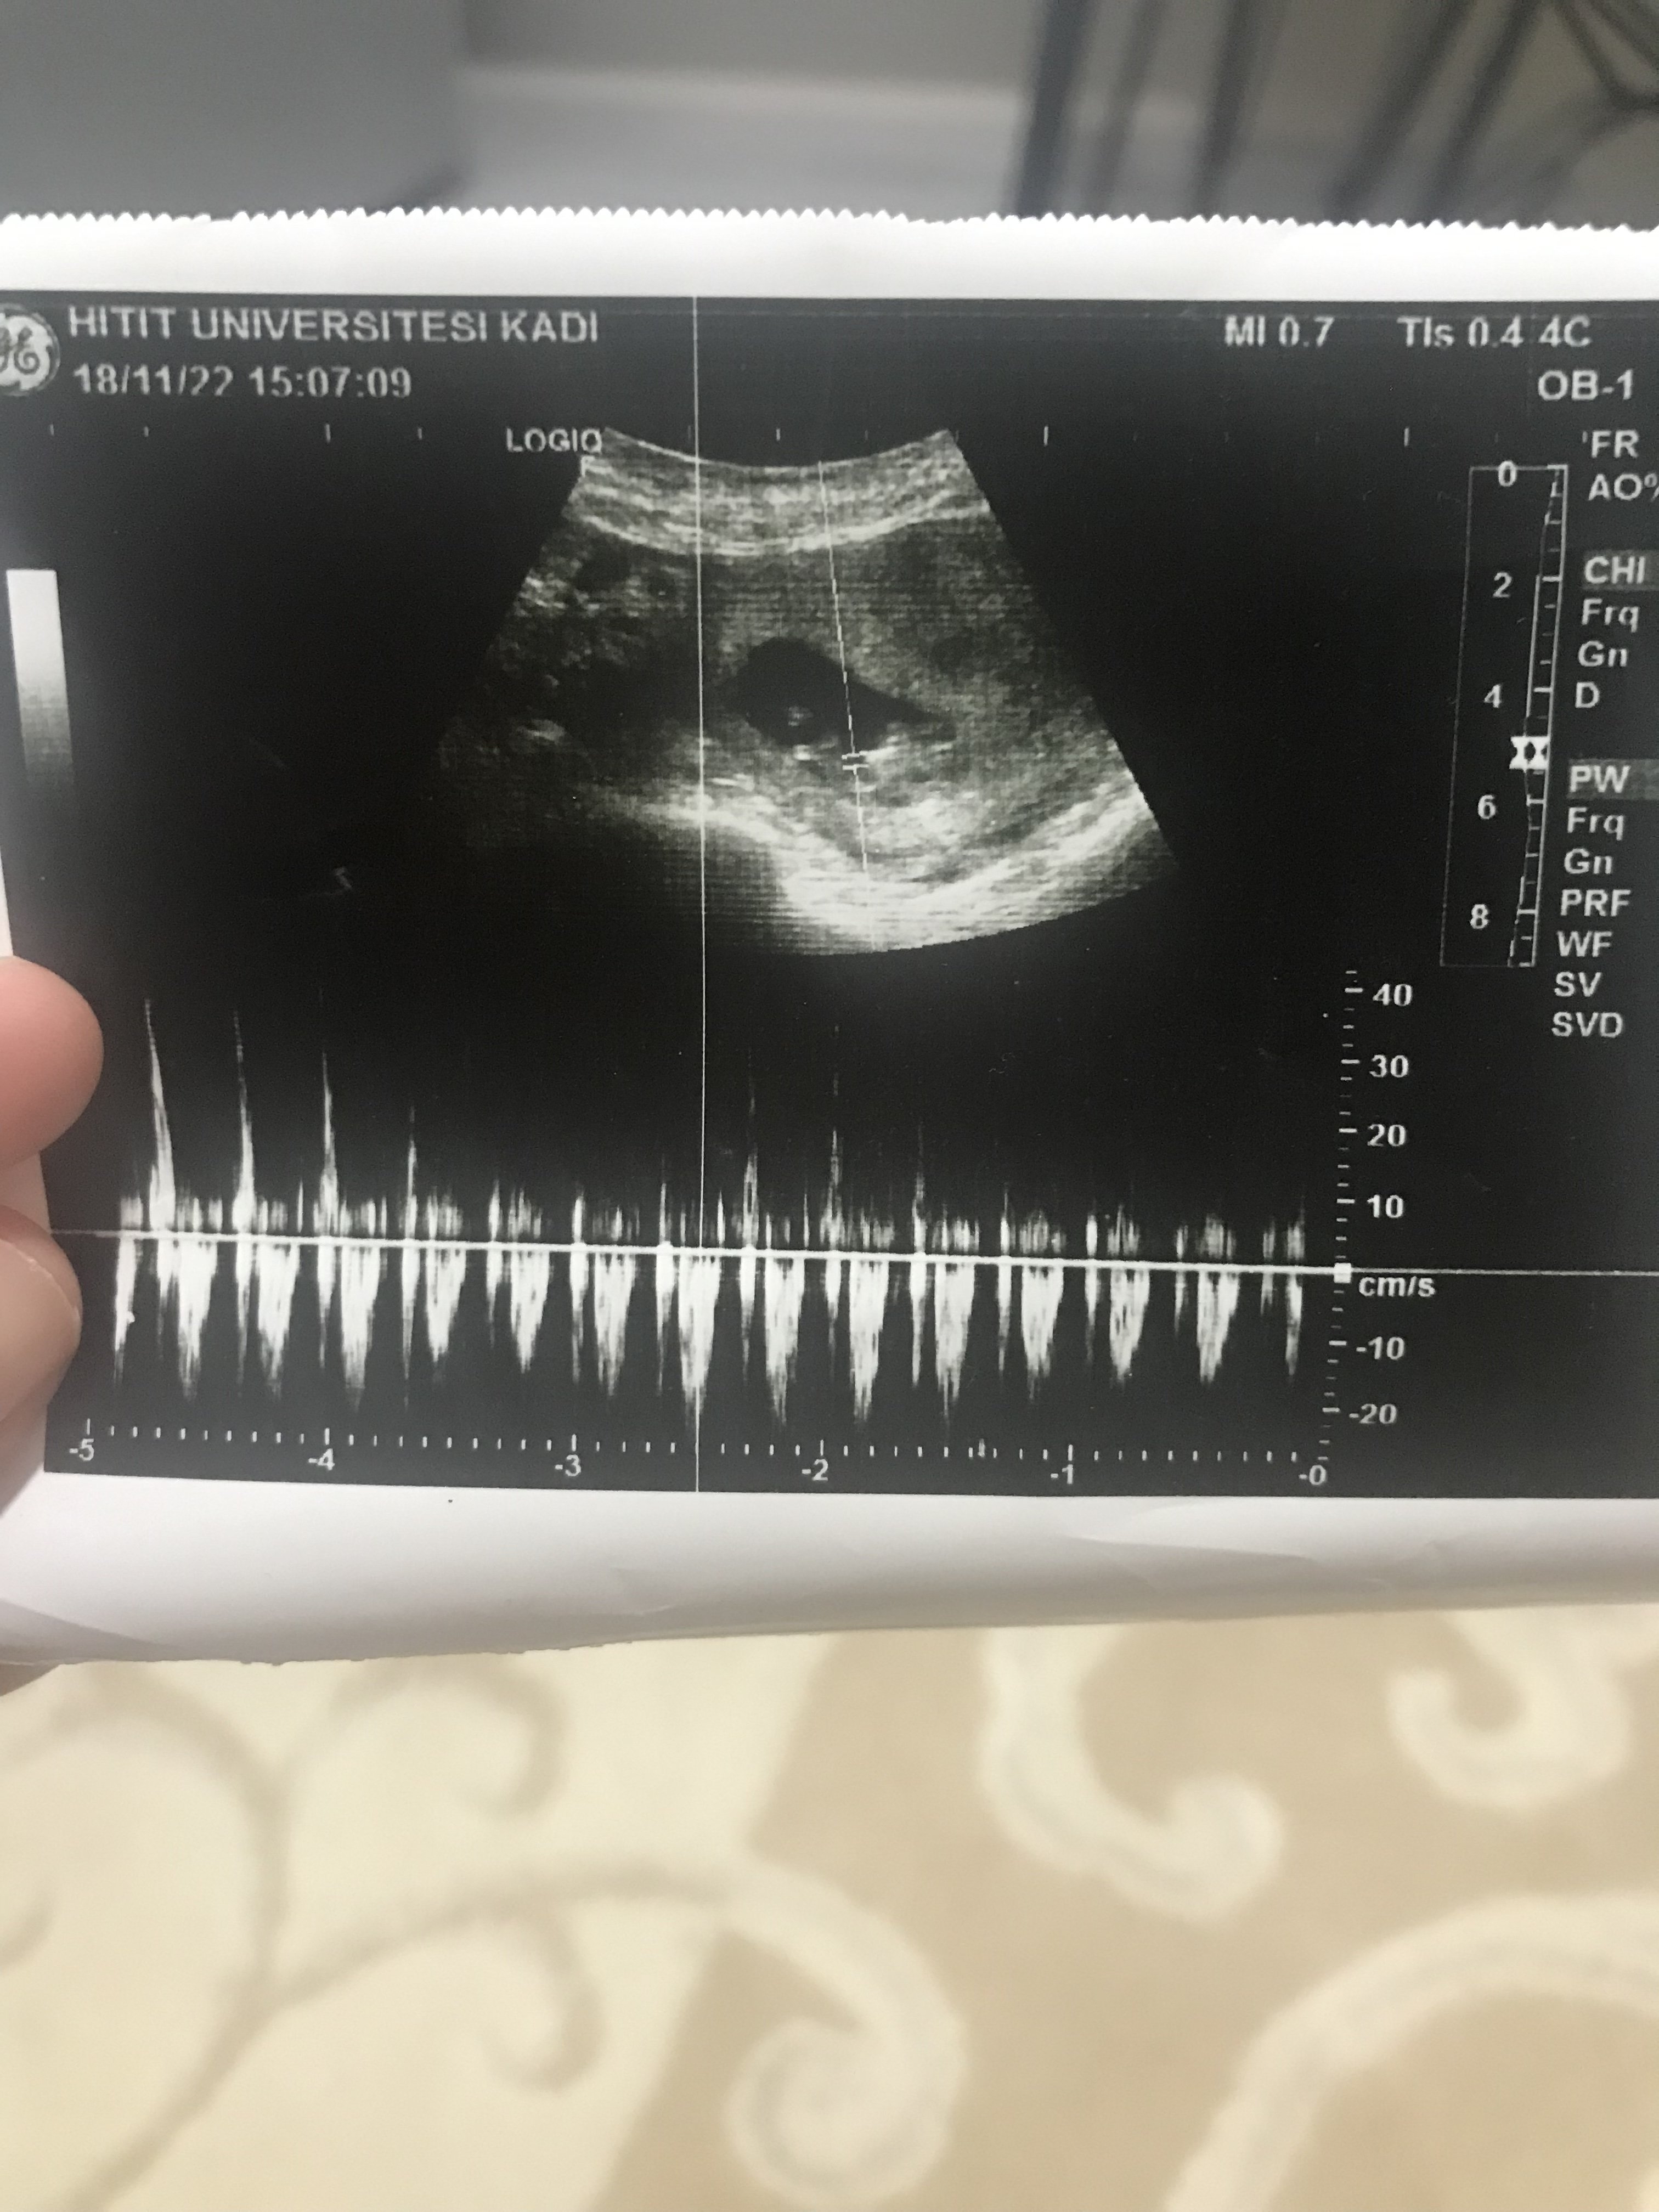

H Hayırlısı Hamiş Melek 18 Kasım 2022 #171 SadmiN' Alıntı: Malesef hayatım çok sisli ve buğulu bir şey anlaşılmıyor aşka resimler geldikçe ekleme yap lütfen değerlendirme yapalım. Genişletmek için tıkla ... Ekli dosyalar 8702970C-55CF-4AFD-A06E-CBD089D5EFFA.jpeg 1,6 MB · Görüntüleme: 181

SadmiN' Alıntı: Malesef hayatım çok sisli ve buğulu bir şey anlaşılmıyor aşka resimler geldikçe ekleme yap lütfen değerlendirme yapalım. Genişletmek için tıkla ...